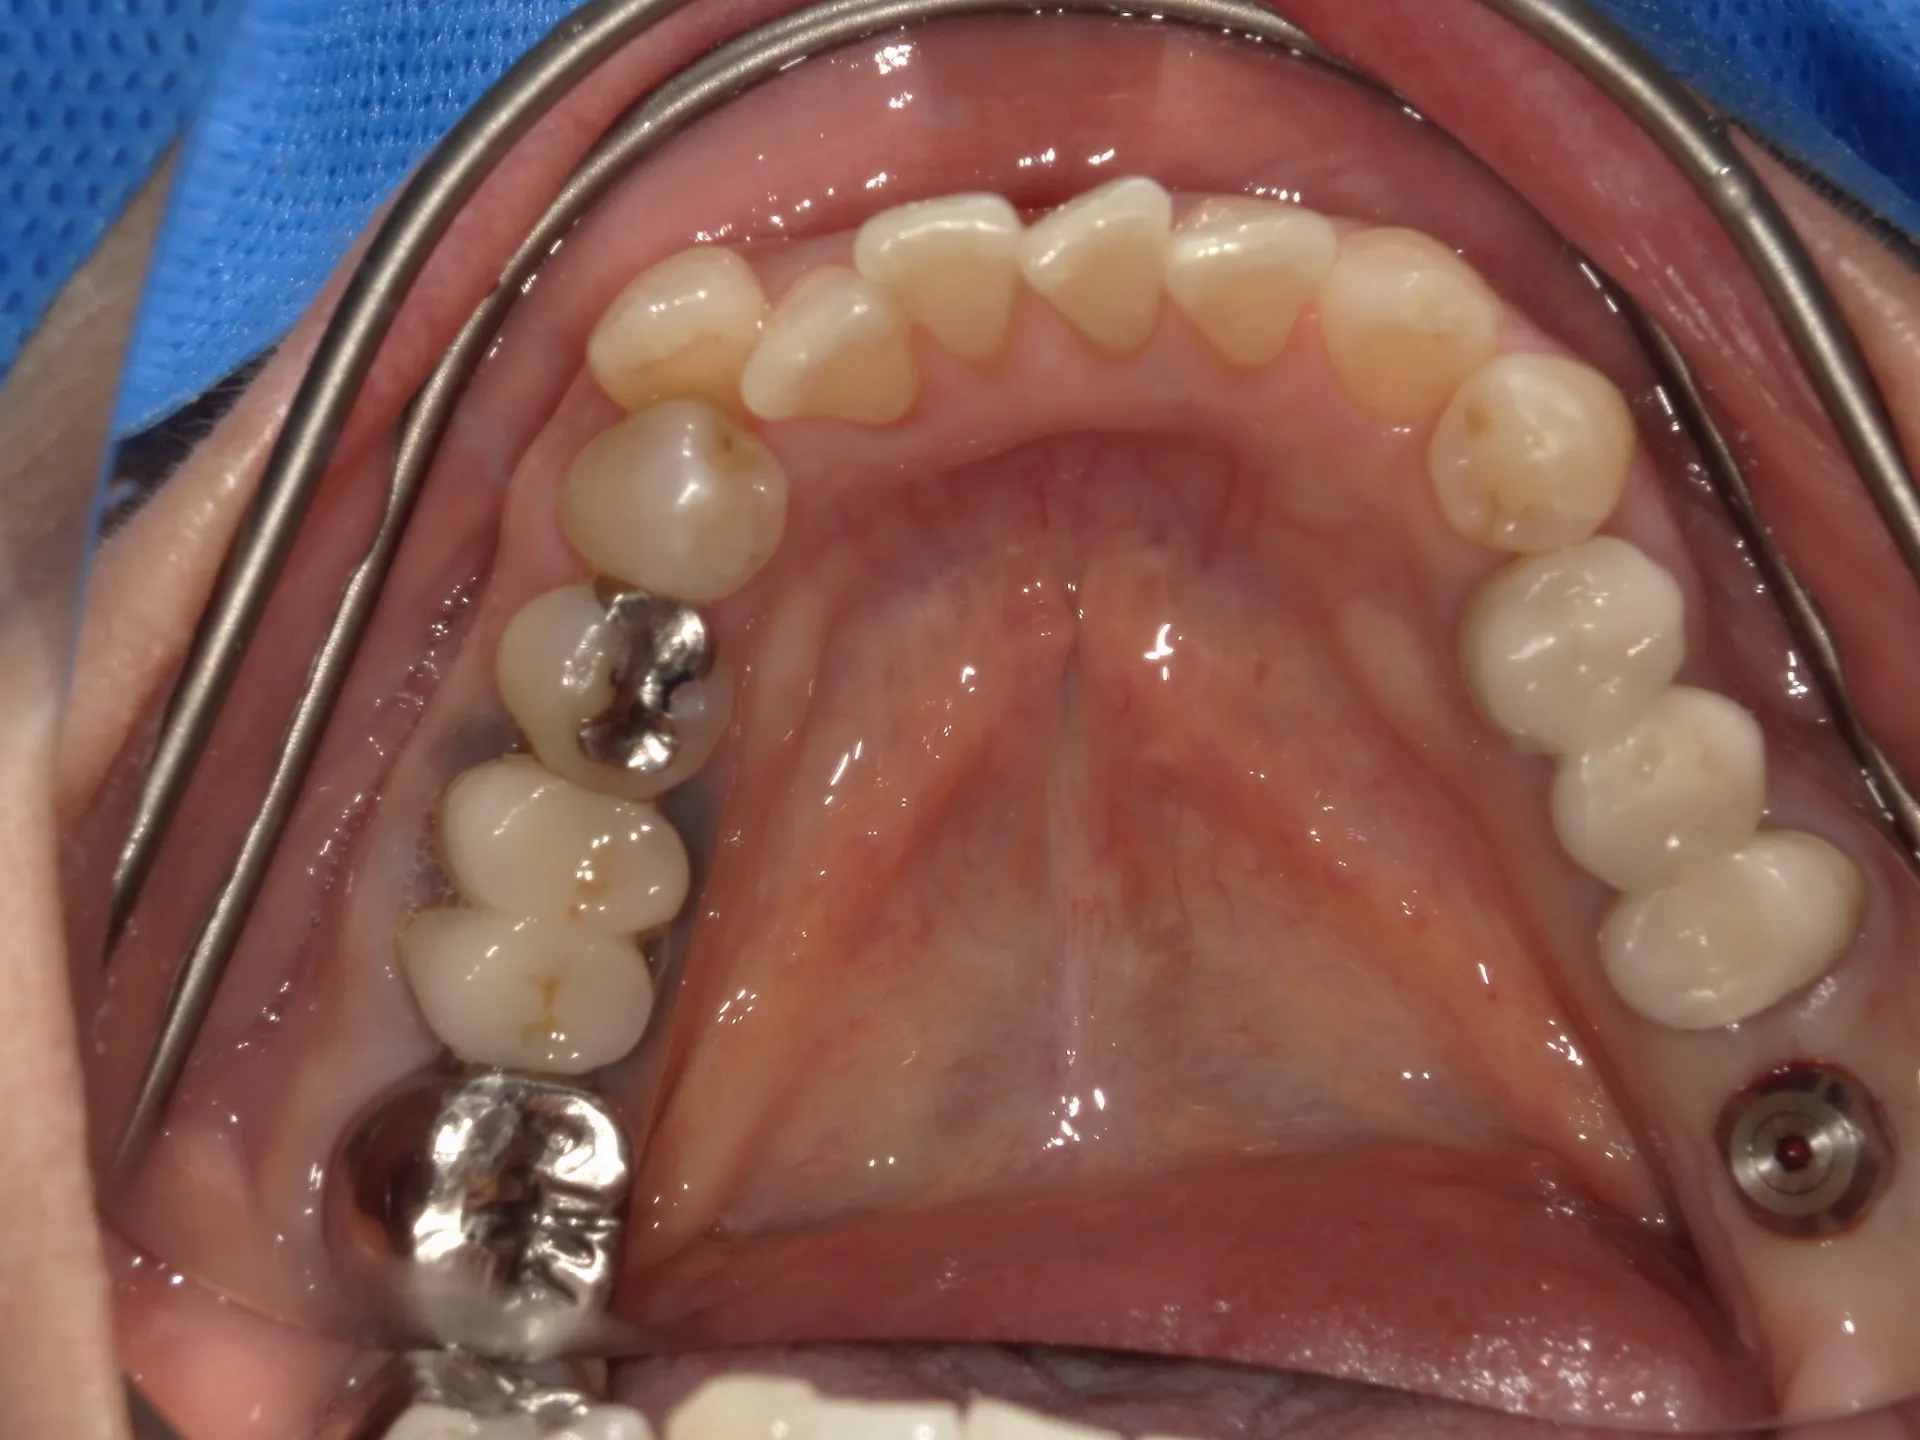

歯茎のメタルタトゥー(歯肉の黒ずみ)は、主に金属の被せ物や土台から溶け出した金属イオンが歯肉に沈着することで起こります。特に古い銀歯(いわゆるパラジウム合金など)が原因になることが多いです。

① 原因金属の除去・交換

古い銀歯や金属土台を除去

セラミック(ジルコニアなど)やファイバーコアへ変更